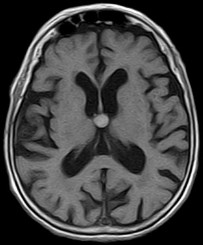

August 2005 - Colloid Cyst

Colloid cysts are benign, epithelial lined lesions, usually located antero-superior to the third ventricle (between the columns of the fornices). They supposedly originate due to an infolding of the neuroepithelium. These cysts may also occur in the choroid plexus of the lateral ventricles, subarachnoid space and brain parenchyma. They comprise approximately 2% of all glial neoplasms. Patients may present with headaches, sudden transient paralysis of both lower extremities, urinary incontinence, personality changes and/or dementia.

• On MRI

• These lesions may be either hypointense or hyperintense on either T1W or T2W images. The variability is due to it's contents. They may contain mucoid material, blood/hemosiderin, macrophages, cholesterol crystals, CSF and various ions (Na, Mg, Ca, Cu, Si, Al, Fe, P).

• Occasionally they may contain serous fluid and follow CSF signal characteristics.

• The lesions are thin walled and peripheral enhancement is common.